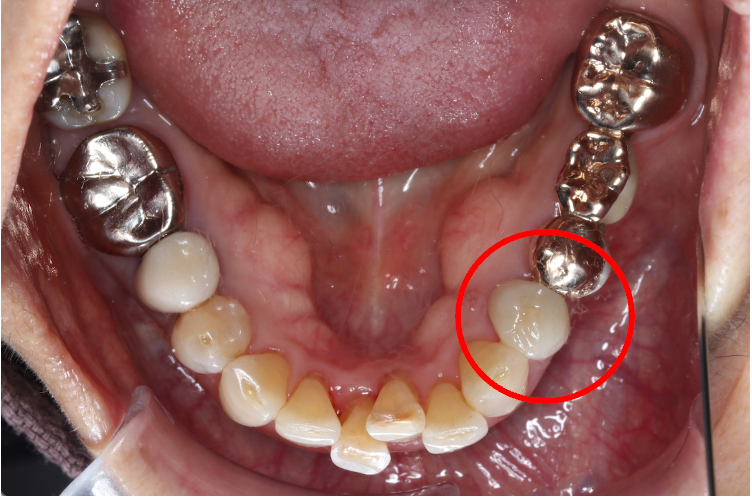

セラミック症例④

年齢50代男性

治療期間1ヶ月

治療内容セラミックインレー、クラウン

治療箇所

左下7番 左上4番、5番、7番 右下6番 右上5番

治療費用600,000円